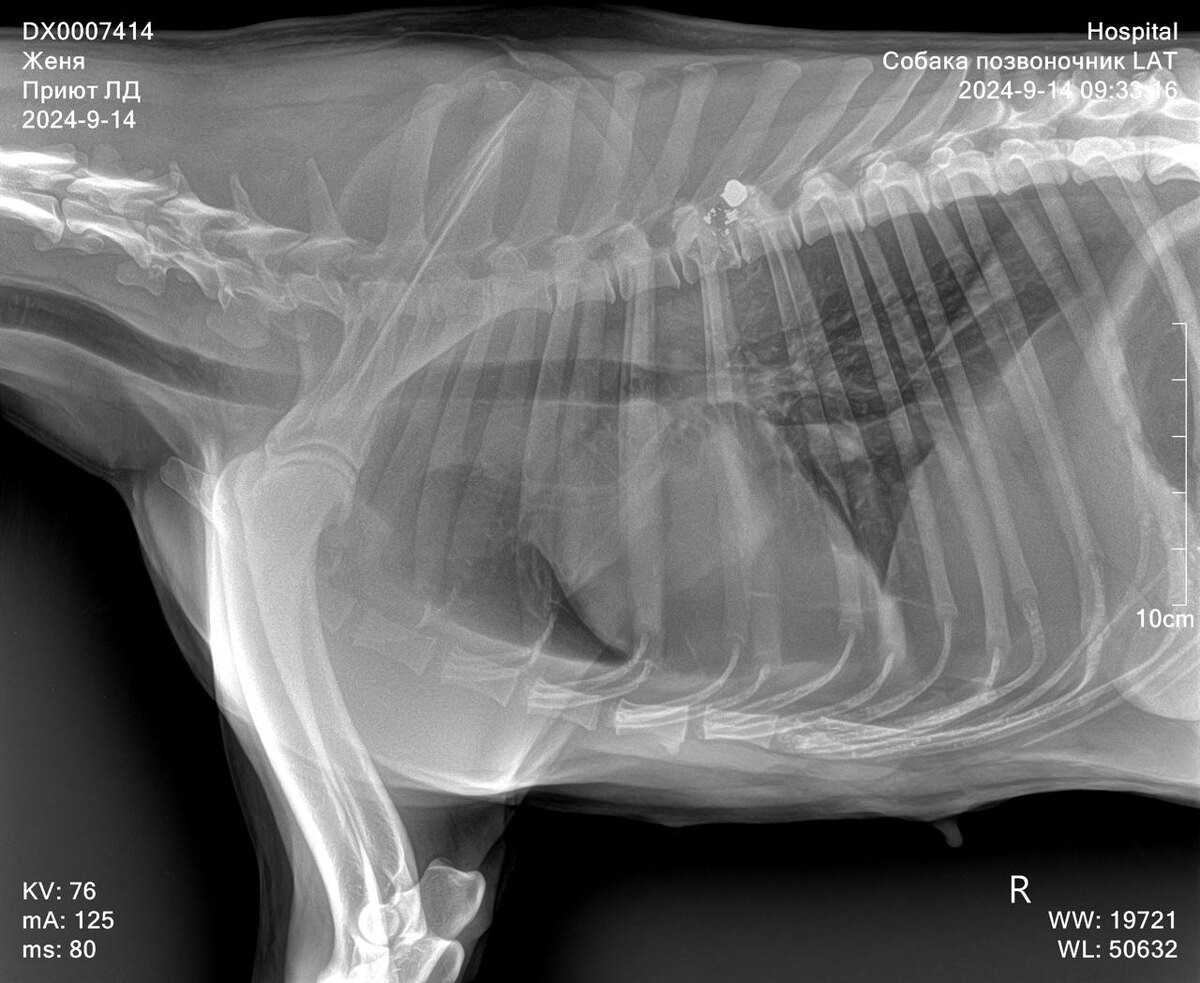

Лохматую белую с черными пятнами собаку нашли на улице в районе частных домов. Собака не встает, тяжело дышит, вся трусится, от воды и еды отказывается.

Предположили, что собаку сбила машина, но нет, на рентгене в клинике выяснили, что в собаку кто-то стрелял и пуля застряла в опасной близости от позвоночника.

Женя, так назвали собаку, осталась на стационаре, ей провели дополнительные обследования и отправили на консультацию к хирургу. К сожалению, Женя останется спинальником, на передние лапы она после лечения стала опираться, задние так и остались неподвижны... Ей нужна будет коляска для прогулок и финансовая помощь для оплаты счетов из клиники. Долг 7418 руб